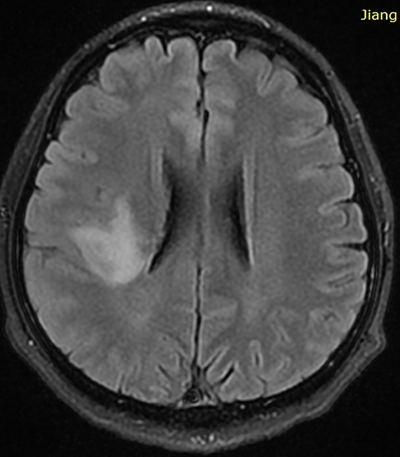

1、40多岁林先生,5个月前突发左侧面部麻木,随之出现左上肢麻木由左手向左肩发射及下肢麻木,经检查发现右岛叶占位,头颅MRS提示肿瘤性病变(低级别胶质瘤)